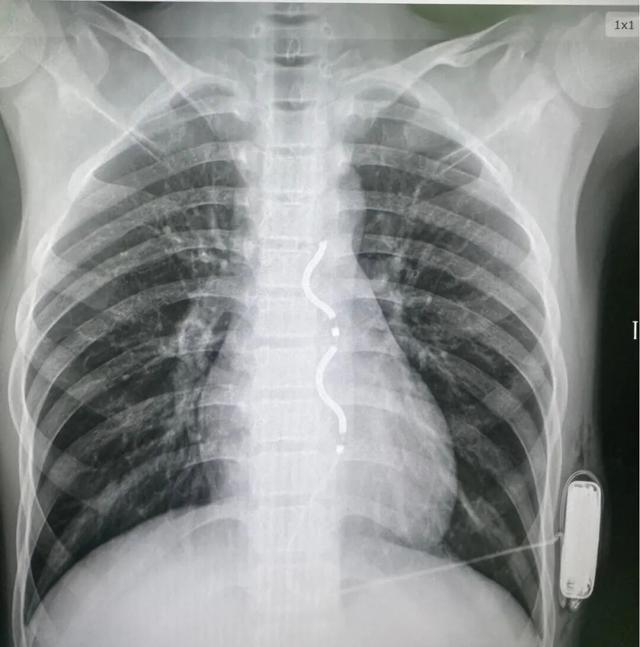

手术当日,在心脏外科、麻醉科的紧密配合下进行,石琳精心安排手术步骤,江河副主任凭借精湛的技术,精准地将除颤电极导线沿胸骨旁皮下隧道放置到预定位置,并在患儿左侧胸壁皮下制作囊袋放置ICD脉冲发生器。整个手术过程顺利,术中测试显示除颤系统感知良好,除颤功能有效,成功为患儿的心脏安装了“体外守护神”。

EV-ICD影像